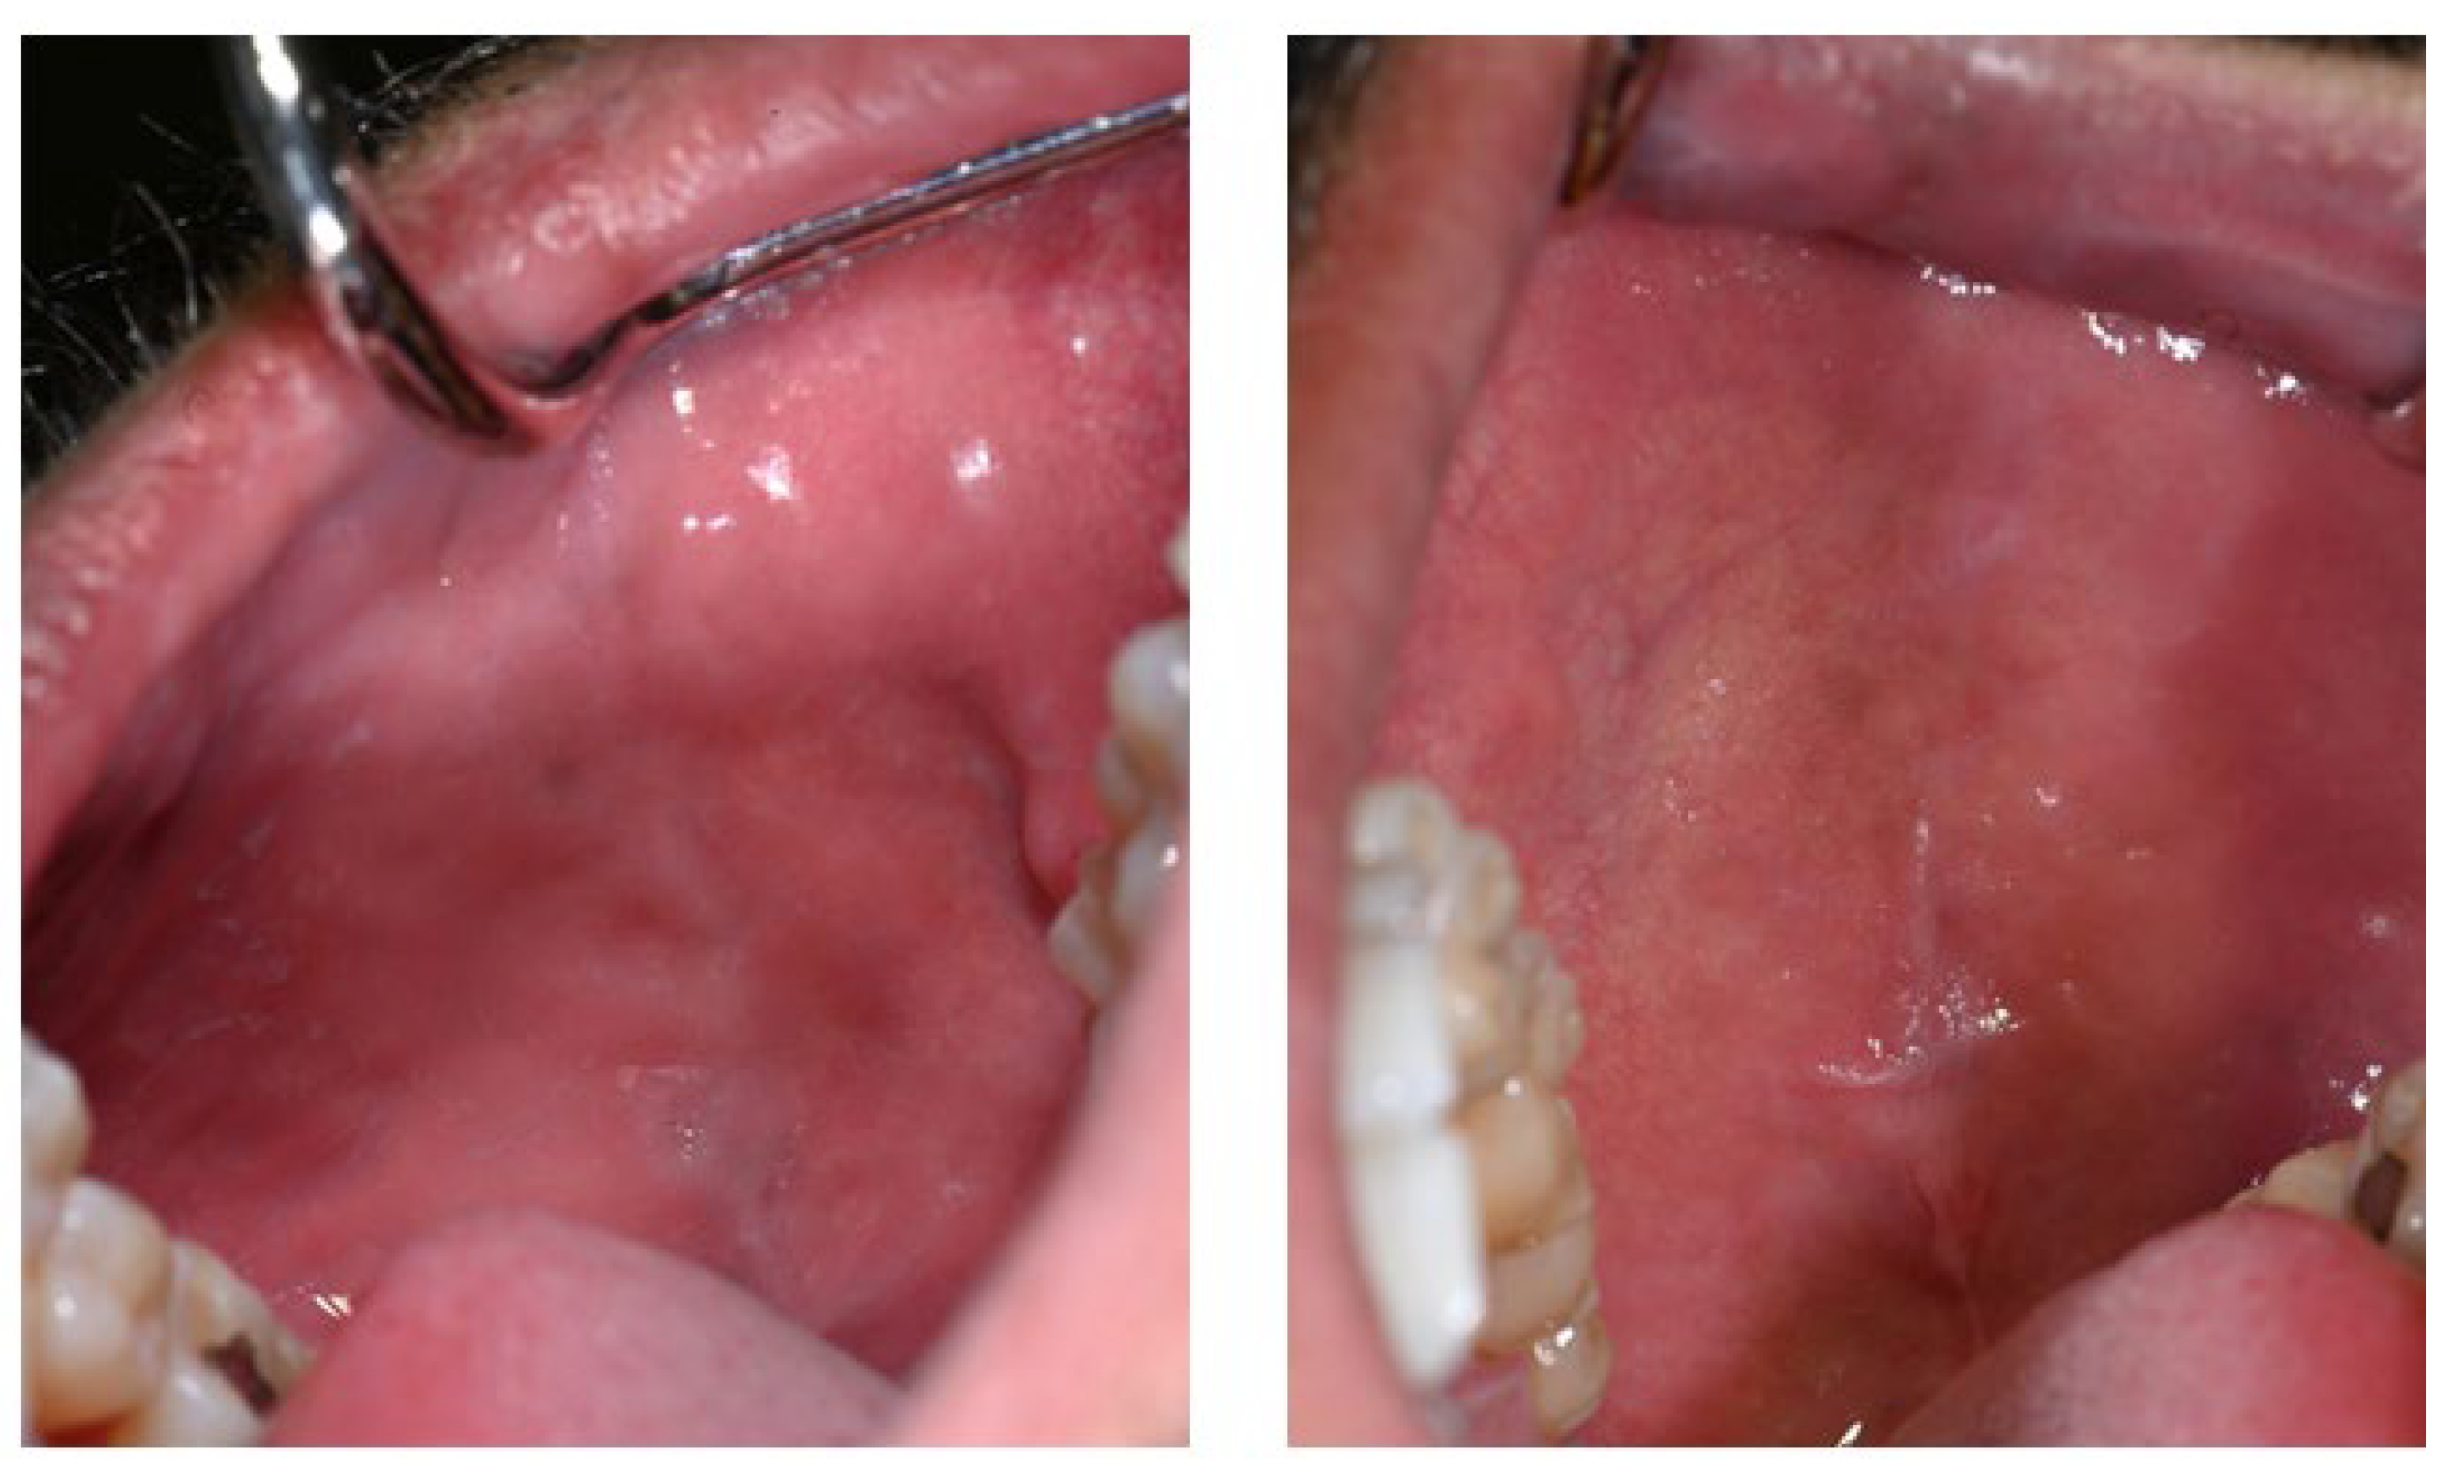

Additional pigmented areas were observed on the left and right buccal mucosa with irregular shape and poorly defined borders (Figure 3).

Figure 3.

Pigmentations on the buccal mucosa during the application of Melanotan II.

The first noticeable signs of size reduction and decreased pigmentation intensity were observed after 28 days, most prominently on the buccal mucosa (Figure 5).

Figure 5.

Buccal mucosa 28 days after discontinuation of Melanotan II application.